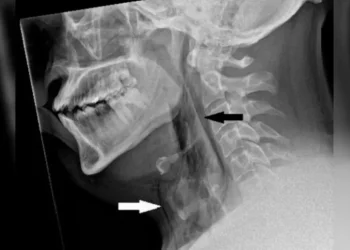

Saiba MaisUm paciente que não teve seu nome divulgado, teve sua traqueia rompida após tentar segurar seus espirros, pressionando o nariz...